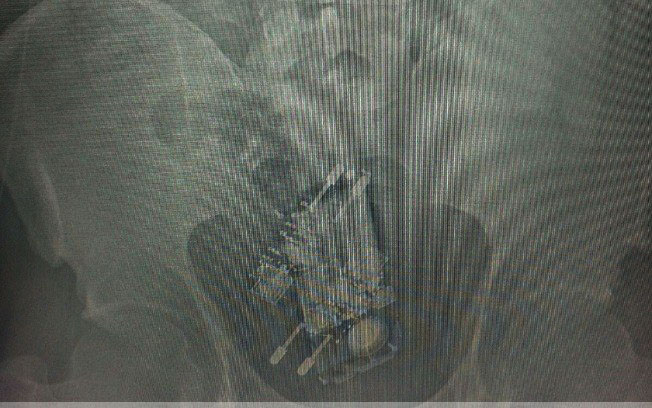

Raio-X detectou presença de aparelho celular e dois carregadores no reto de presidiário, em BrasíliaRaio-X detectou presença de aparelho celular e dois carregadores no reto de presidiário, em Brasília

Um detento do Complexo Penitenciário da Papuda, em Brasília, foi flagrado nesta terça-feira (13) com um aparelho celular e dois carregadores no reto ao retornar da saída especial para comemoração do Dia das Crianças.

O detento, que não teve o nome divulgado, foi encaminhado ao hospital regional da Asa Norte onde passou por um procedimento cirúrgico para a retirada dos objetos. ultimosegundo